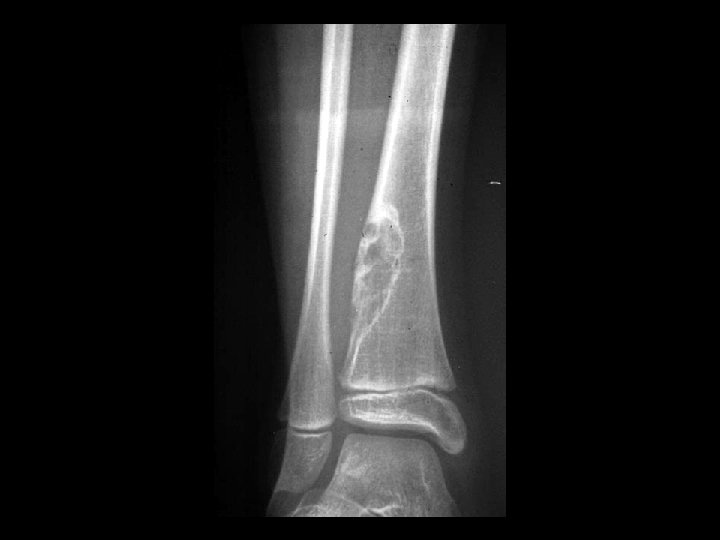

Osteosarcoma • Findings: – Aggressive lesion of the distal tibia in a skeletally immature person – “cloud-like” appearance = calcified osteoid matrix – Intense periosteal reaction – Soft tissue mass • ddx: – NONE! – This is an Aunt Minnie!